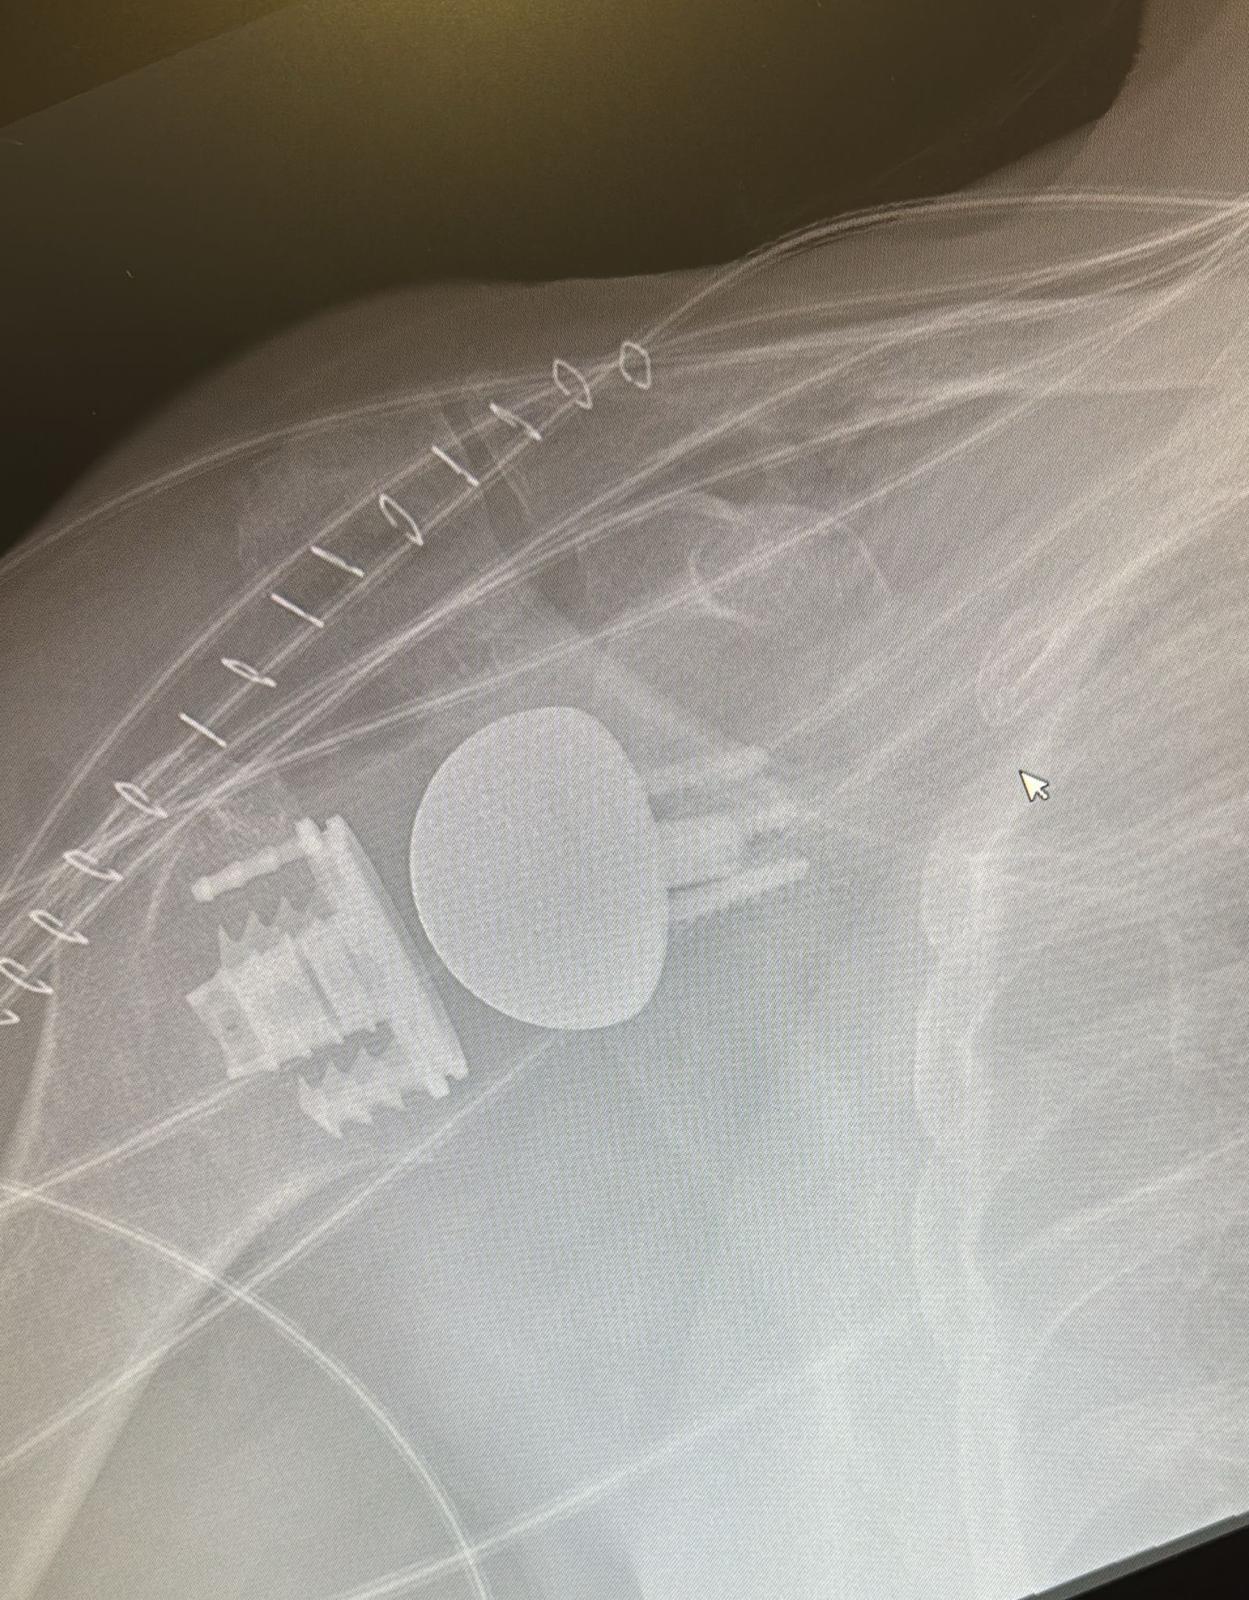

L'Hospital Universitari Sant Joan de Reus ha dut a terme amb èxit dues intervencions quirúrgiques d'implantació de pròtesis d'espatlla "stemless" o sense tija. Aquest nou disseny de pròtesi és menys invasiu per l'húmer, perquè no es perfora l'os per introduir-hi la tija, com en el tipus estàndard. Això permet respectar més l'estructura òssia, i facilita les cirurgies peri-implant - d'ossos prop d'un implant -, o de recanvis per afluixament.

La col·locació d'aquest tipus de pròtesi ve determinat per unes característiques particulars del pacient que es valoren abans i durant la cirurgia. En cas que la qualitat òssia no sigui suficient, l'equip opta per la pròtesi estàndard amb tija llarga. Els dos pacients intervinguts a Reus van rebre l'alta mèdica l'endemà de les cirurgies sense cap complicació mèdica, amb els controls analítics i les radiografies postoperatòries correctes.